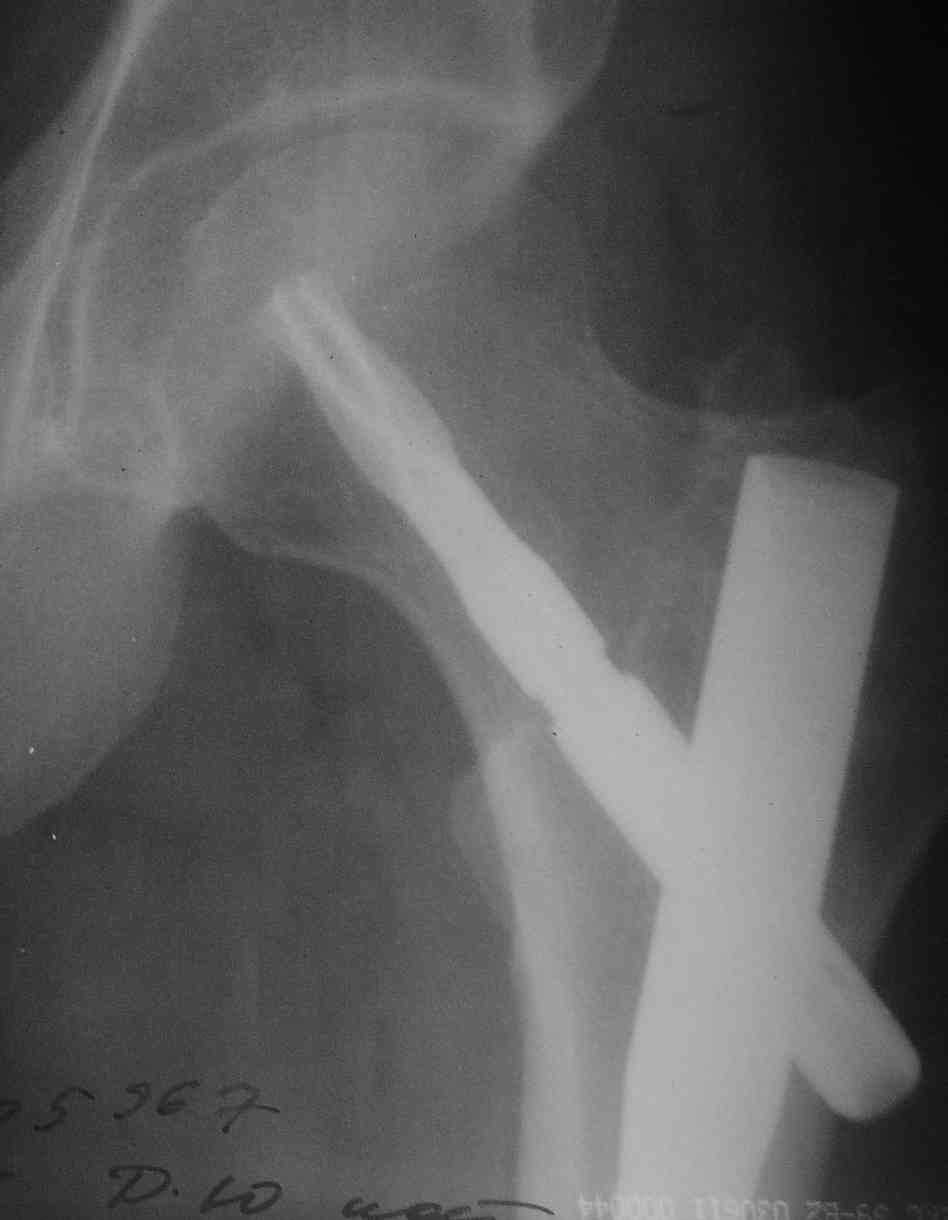

Молодой мужик, была множественная травма. Снимок перед удалением вот.

Действительно клинок не был заблокирован даже близко. Тогда вопрос: как на первой операции вы сняли "отвертку", вкрученную в клинок, которая может отсоединиться, только если клинок заблокирован?

Клинок не заблокирован, т.е. пациенту и вам повезло, что он не мигрировал кнаружи. Клинок может быть заклинен в гвозде, вряд ли намертво, или мешает костная ткань, вросшая в промежуток между самим лезвием и "телом" клинка. Саша, уверен твоей смекалки должно хватить для решения этой задачи, и ты нам об этом еще расскажешь!